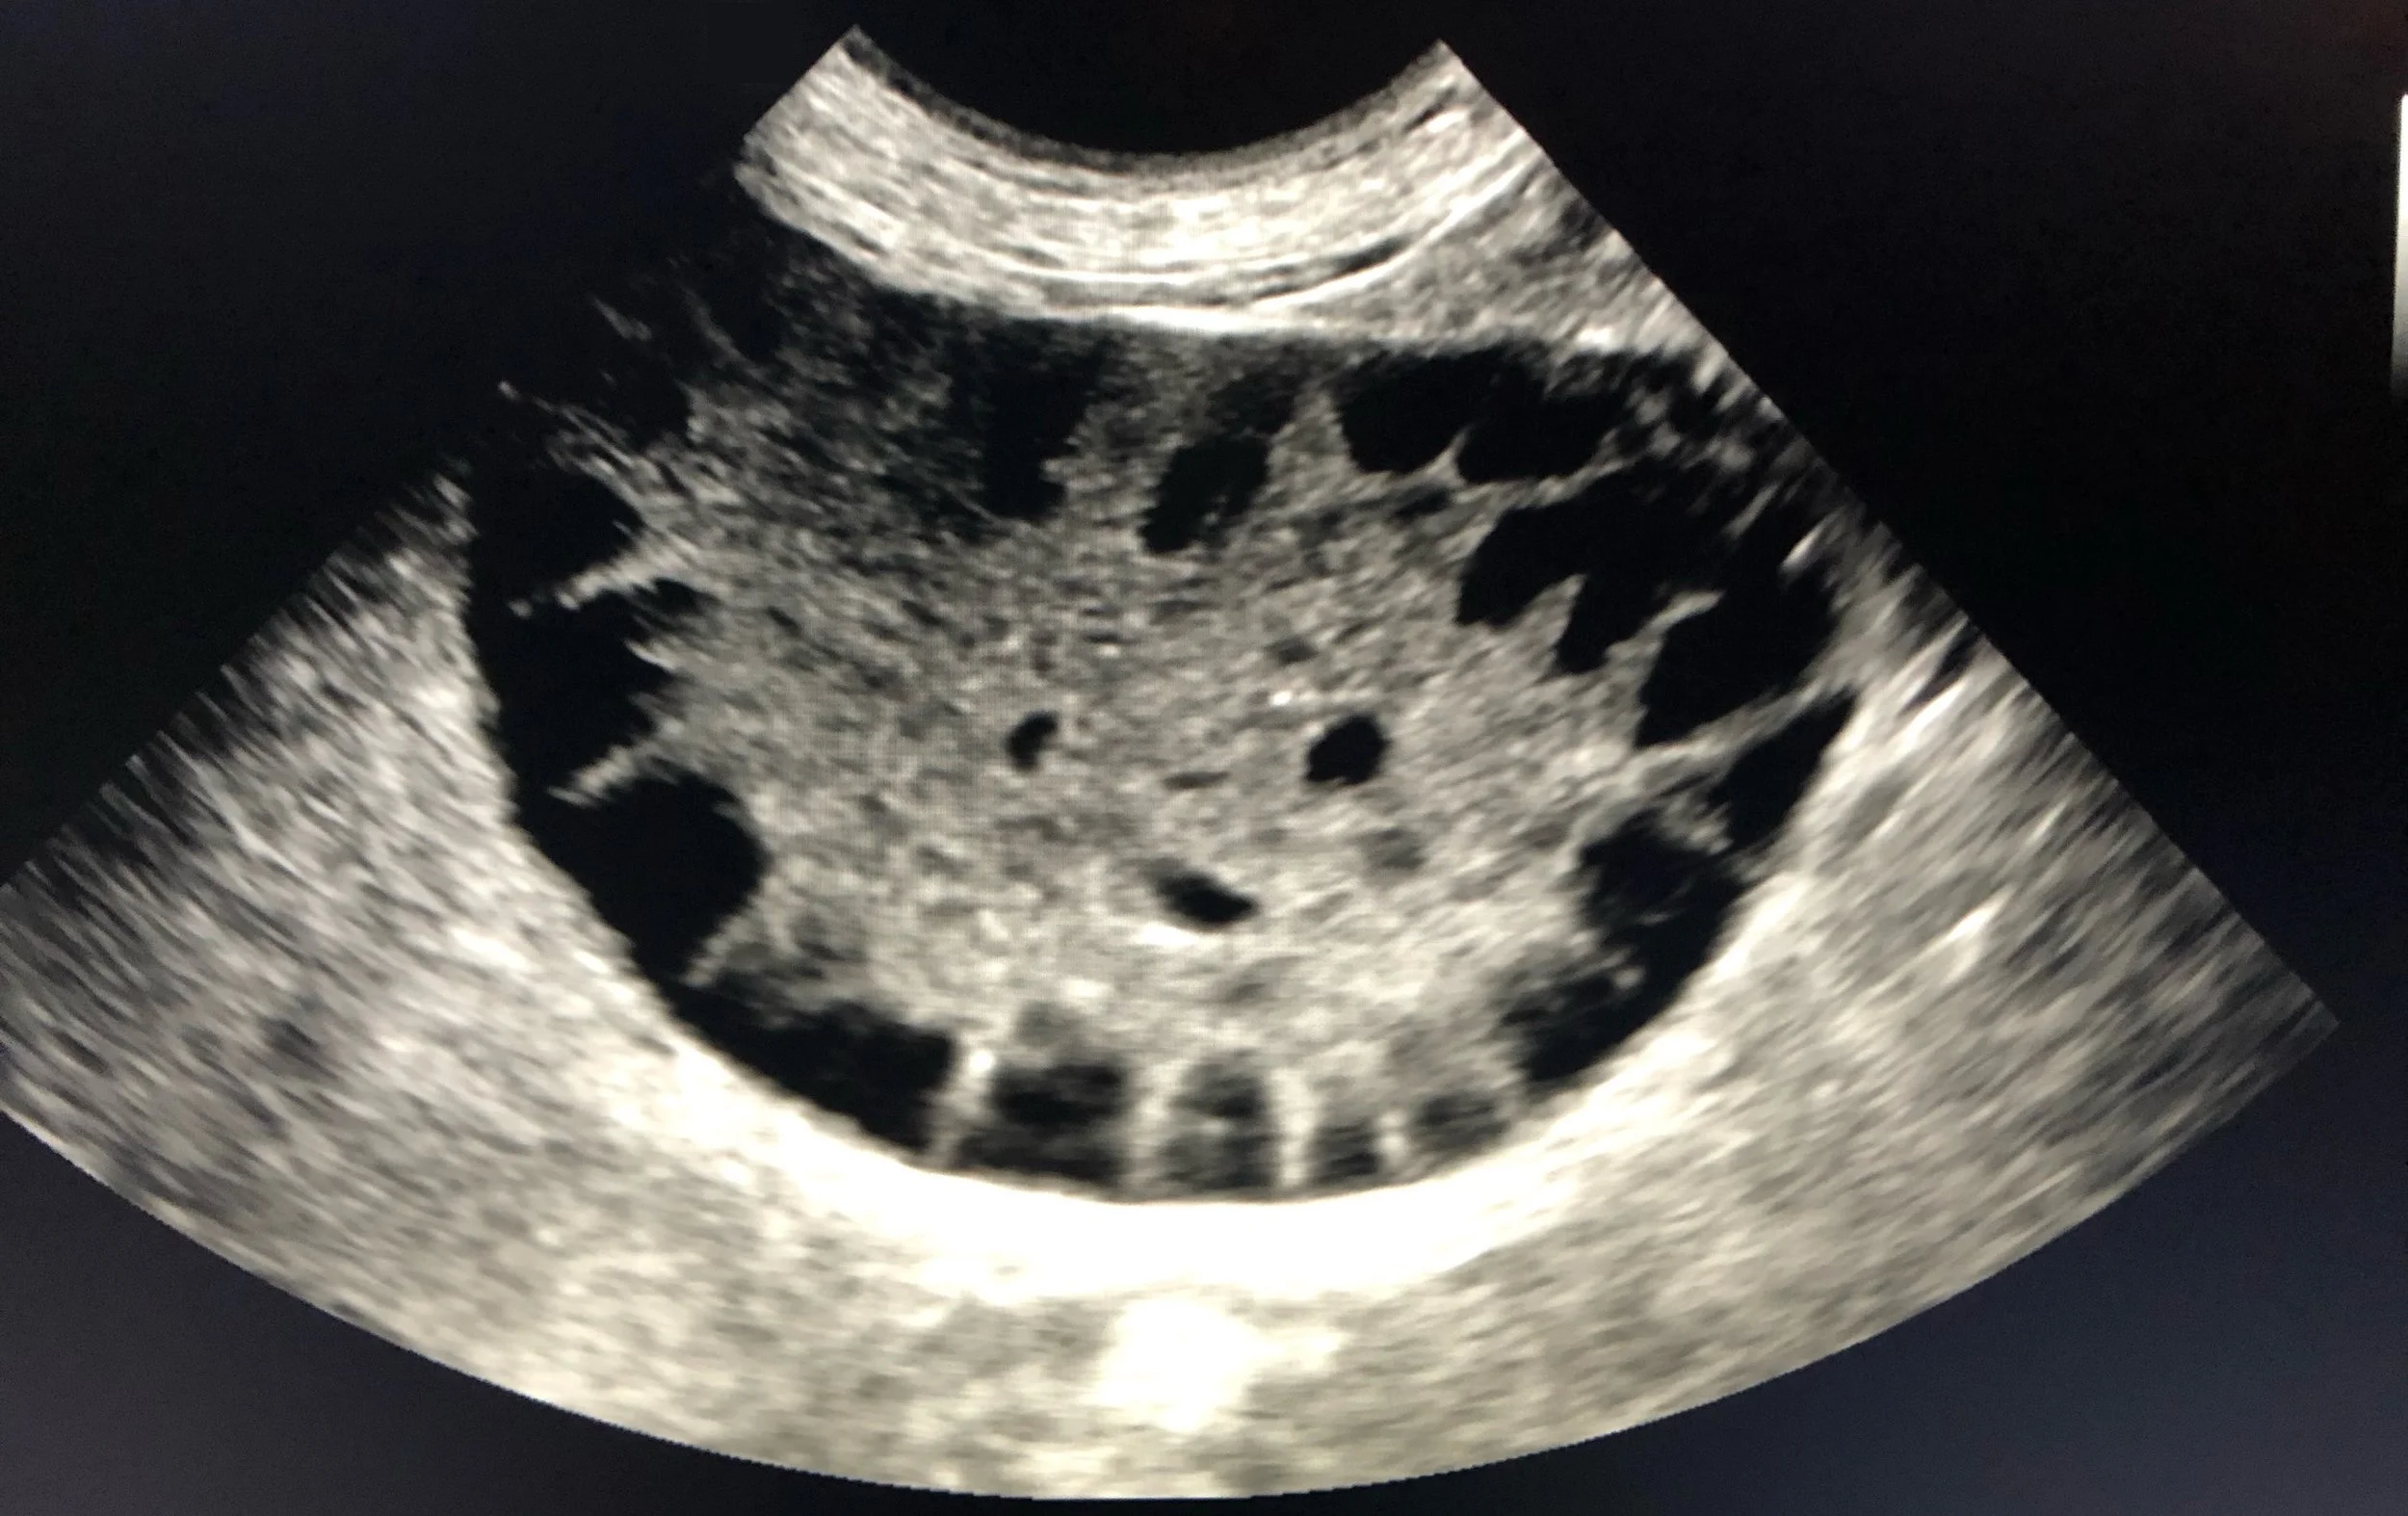

gallbladder mucocele

Mobile Ultrasound

Clear, confident abdominal and thoracic ultrasounds performed in your office, on your terms. Thyroid and musculoskeletal scans available too.